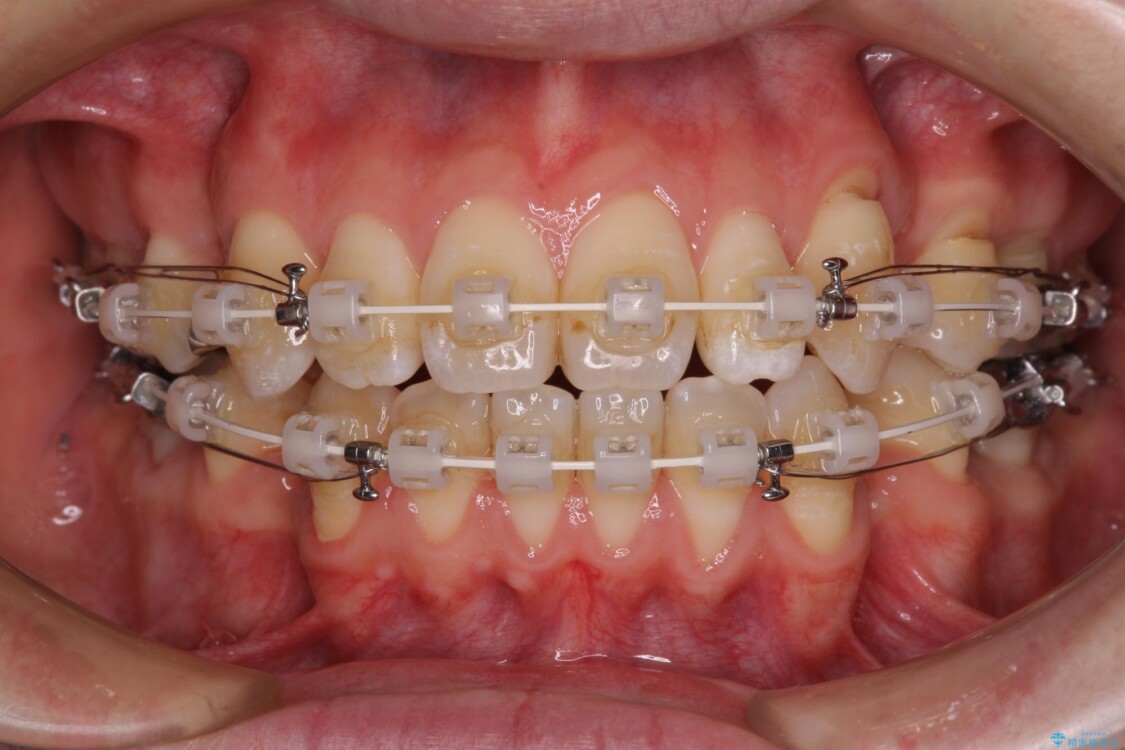

装置は、透明感のあるクリアブラケットとホワイトコーティングされたワイヤーを使用した、目立ちにくい審美装置を選択。

周囲に気づかれにくく、日常生活にも自然に溶け込みます。

治療途中

• 口元の突出感を改善!目立ちにくいワイヤー矯正で自信を持てる自然な横顔に 治療途中画像